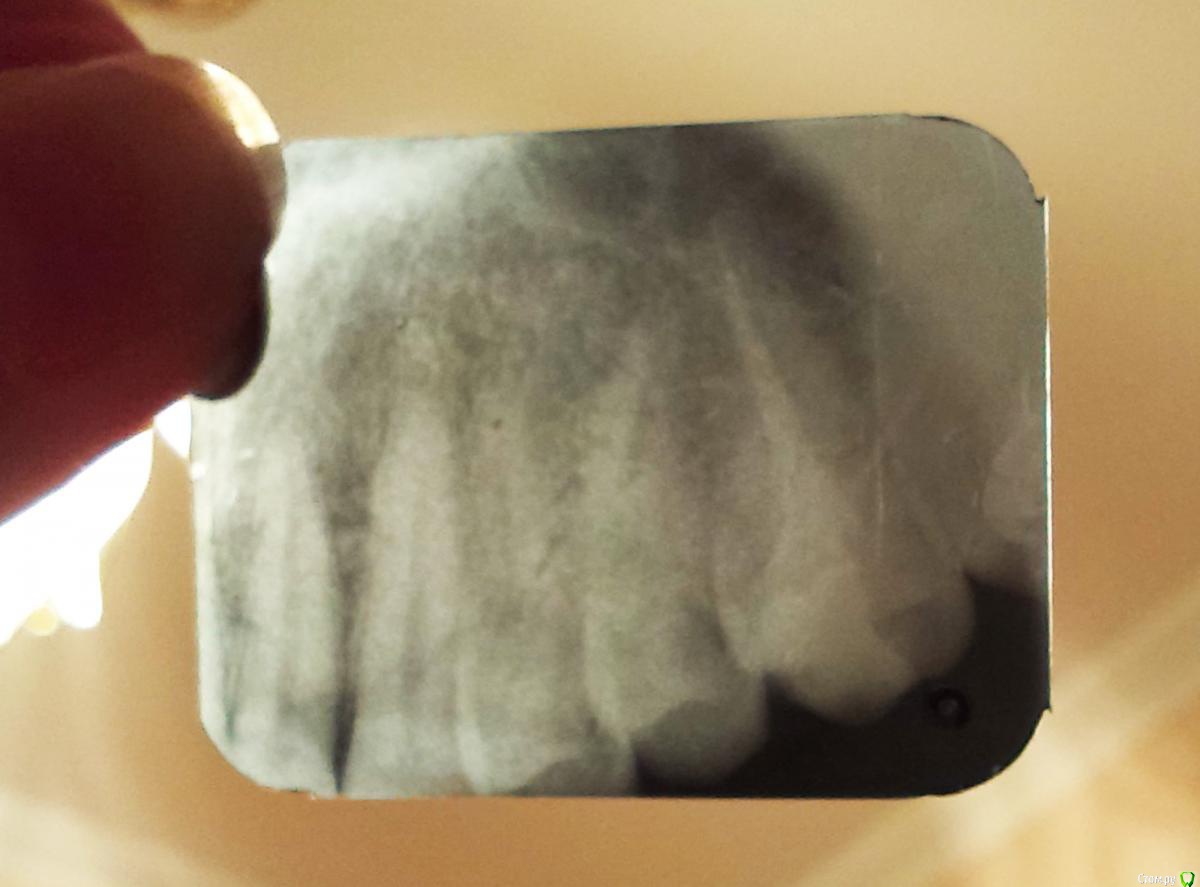

Scream Опубликовано 29 апреля, 2015 Автор Поделиться Опубликовано 29 апреля, 2015 Если плохого запаха нет во рту, если сильно не болит и т.д. - то все будет норм. Метрогил можно до 7 дней наносить без проблем. Коричневое что сверху (ворсинки) -это альвожил. Его я убрал бы, если не уберете - то само постепенно уйдет. Убирать лучше у доктора, хотя у меня пациенты и сами убирали. Но мне трудно судить в Вашем случае-все индивидуально у всех, сами понимайте. Здравствуйте! Спасибо за ответ! Запаха нет, да и боли примерно на 50% поменьше. Иногда тянет и отдает в передние зубы, редко (пару раз в сутки) боль глубокая, сильно, но секунду-две - и отпускает. Чувство распирания присутствует. В целом вполне терпимо, улучшения есть, я снова человек Мажу метрогилом. Альвожил вынимать боюсь - мне кажется он врос в лунку.Сделала вчера снимок. Прилагаю к сообщению. Качество ужасное, мелкий (4х4 см), плюс сделали криво, эх, местная медицина.... Постаралась максимально увеличить, чтобы Вам было видно. Дежурный врач посмотрел и сказал, что удаление было серьезным и по снимку сломана какая-то перегородочная кость (?), если я правильно поняла. Делать, якобы, ничего не надо, зарастет или вылезет сама. Признаюсь, перспектива второго варианта меня пугает. Если она вдруг вылезет, то куда мне бежать? В местную стоматологию к обычному врачу или ехать к ЧЛХ, который делал удаление? Это ведь серьезно, я так понимаю и будут резать? А может ее сразу удалить, пока совсем не заросло?И еще вопрос, если можно: если эта кость все-таки заживет так, то может она мешать имплантации в будущем? Благодарю! Ссылка на комментарий

rivezico Опубликовано 29 апреля, 2015 Поделиться Опубликовано 29 апреля, 2015 Сделайте другой снимок, тут непонятно. Ссылка на комментарий